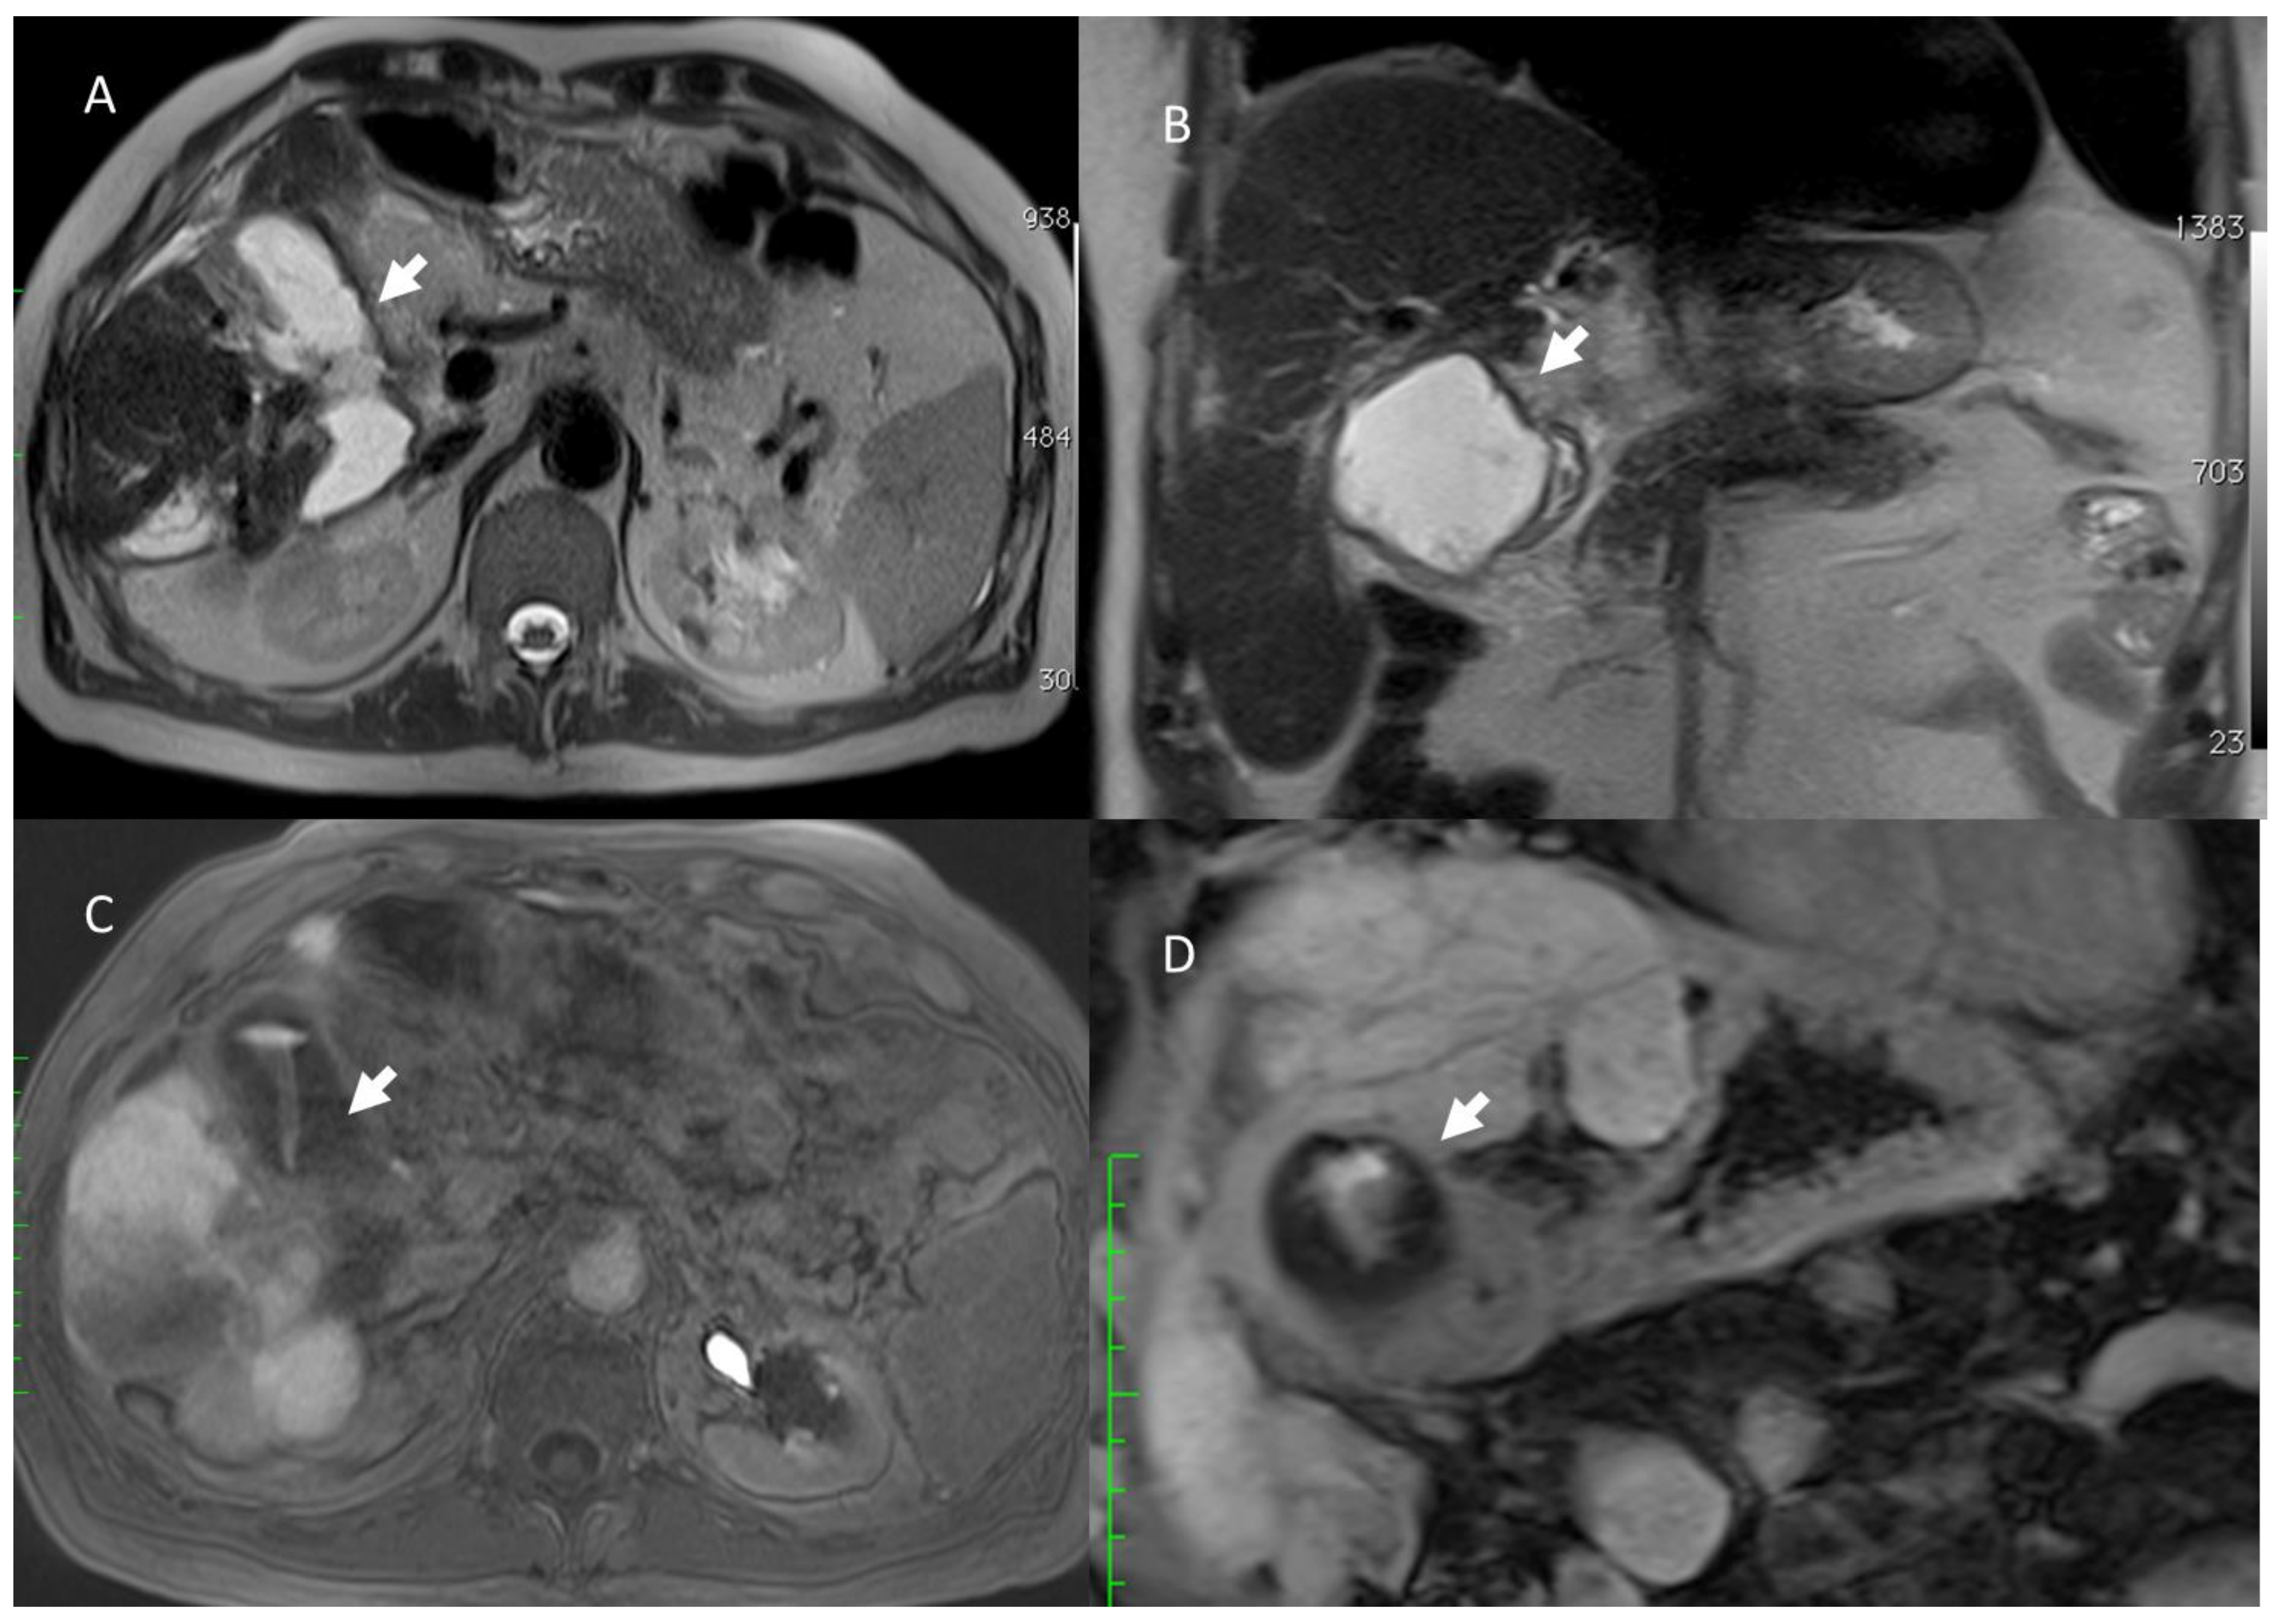

- Granata, V.; Fusco, R.; Catalano, O.; Piccirillo, M.; De Bellis, M.; Izzo, F.; Petrillo, A. Percutaneous Ablation Therapy of Hepatocellular Carcinoma with Irreversible Electroporation: MRI Findings. Am. J. Roentgenol. 2015, 204, 1000–1007. [Google Scholar] [CrossRef] [PubMed]

- Granata, V.; Castelguidone, E.D.L.D.; Fusco, R.; Catalano, O.; Piccirillo, M.; Palaia, R.; Izzo, F.; Gallipoli, A.D.; Petrillo, A. Irreversible electroporation of hepatocellular carcinoma: Preliminary report on the diagnostic accuracy of magnetic resonance, computer tomography, and contrast-enhanced ultrasound in evaluation of the ablated area. Radiol. Med. 2016, 121, 122–131. [Google Scholar] [CrossRef]